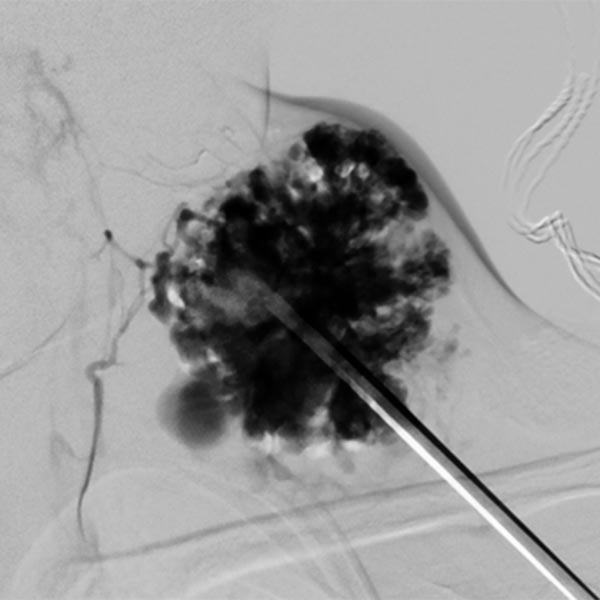

Aufgrund des schnellen Größenwachstums und der rezidivierenden, schmerzhaften Thrombophlebitiden wurde eine Sklerosierungstherapie durchgeführt. Die hier dargestellte Kontrastmittelinjektion über eine eingebrachte Punktionsnadel zeigt eine weitgehende Kontrastierung der venösen Malformation, somit gute Voraussetzungen für eine erfolgreiche Sklerosierungstherapie.

In der digitalen Subtraktionsangiographie nach KM-Injektion über die gleiche Nadel zeigt sich ebenfalls sehr gut die fast vollständige Füllung der venösen Malformation aus dieser Nadelposition. Nur kleine, sehr dünnlumige Kommunikationsvenen stellen sich dar. Daher kann aus dieser Nadelposition ein Großteil der VM sklerosiert werden.